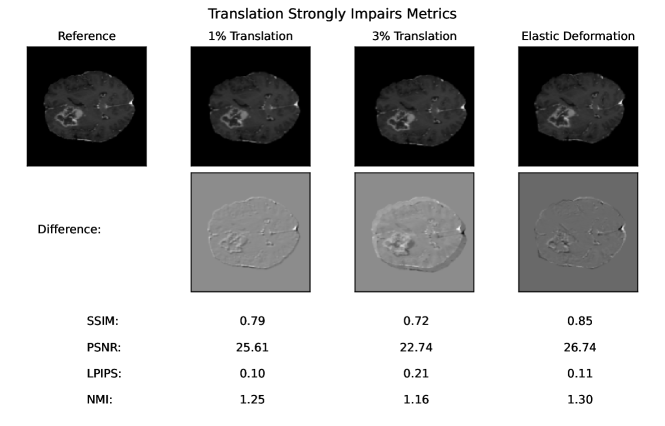

Among the selected distortions, translation and elastic deformation were applied as spatial transforms, that are commonly found, when the reference is not well aligned to the image to be tested. This is frequently the case in image-to-image translation, when the input image was acquired with a different modality or at a different time point. Usually, the patient has moved in between and registration was possibly not sufficient. Translation was modeled as an equal shift of all pixels along the x and y-axis. Elastic deformation was modeled by placing a grid with a decreasing number of points on the image, randomly displacing grid points, and linearly interpolating between the new point positions.

Across all normalization methods, all metrics are very sensitive to translation and not very sensitive to replace artifacts.

5 Adverse Examples

In the following, special characteristics of the analyzed metrics, which can be derived from their definition or the experimental results above, are show-cased. We present adverse examples (see Fig. 2-6), where similarity metrics do not perform as intended or expected.

The experiments and adverse examples demonstrate specific strengths and weaknesses of the analyzed metrics. Although SSIM and PSNR are frequently used for the evaluation of synthetic MR images, they are strongly decreased by constant intensity shifts if no normalization is applied. PSNR is very dependent on the kind of normalization, which complicates its use as a comprehensive metric for comparing studies of different authors. SSIM underestimates blurring and thereby favors blurred or additionally blurred images over other distortions.

As all other analyzed metrics, SSIM and PSNR are both very sensitive to translation, which is rather be caused by misaligned target images, than by dissimilarity of synthesized images. When paired input and target images are not acquired by the same hardware or not immediately at the same time points, special care must be taken, to ensure spatial alignment of input and target images.